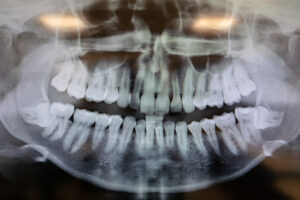

Does Pineapple Juice Help With Wisdom Teeth Removal?

Does Pineapple Juice Really Help With Wisdom Teeth Removal?